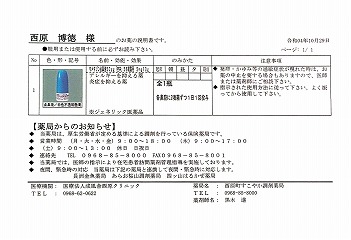

2021.11.13より 西原クリニック 0968-62-0622

22.10.29 鼻炎薬吸引 モメタゾン点鼻液50μg 噴霧用 5mg10g 杏林 56噴霧用

22.09.10

2022.02.19

2021.12.04 西原クリニック処方箋=pdf